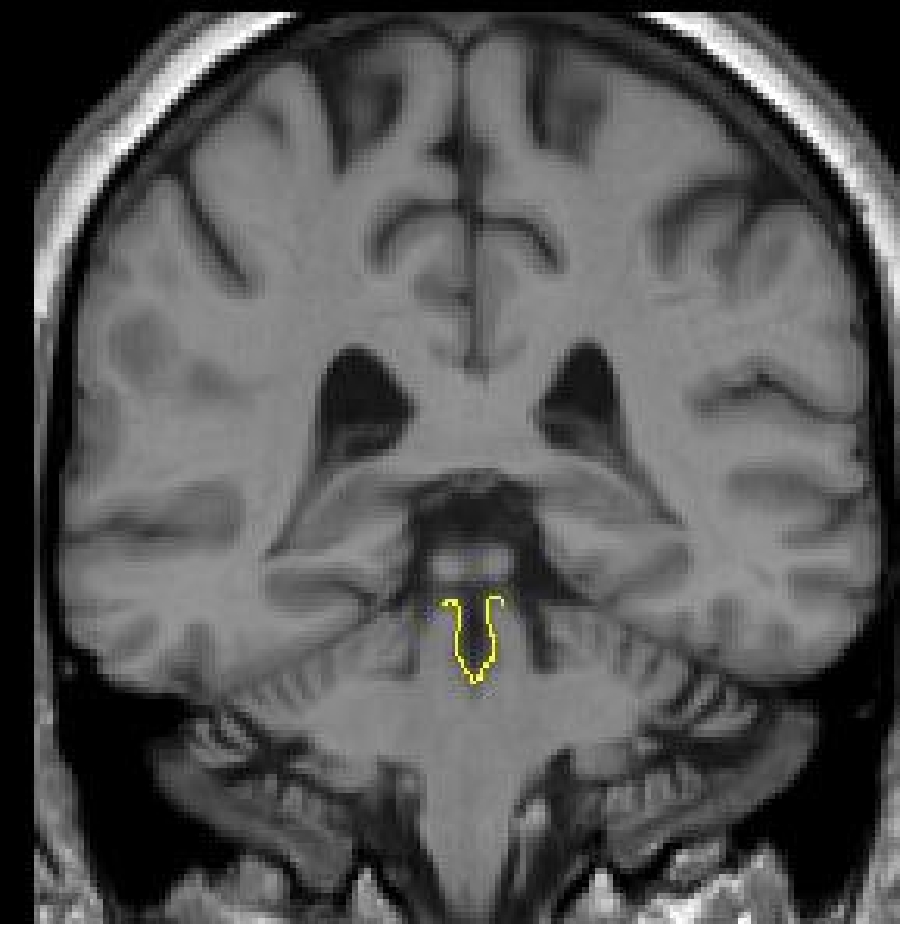

Part

I - cerebral aqueduct

The aqueduct first appears just under the posterior commissure. A histogram

should be taken between the CSF of the aqueduct and the brainstem. However,

because there is so much partial voluming in this area, the histogram will

likely be modified using an intensity contour line. The dorsal border of the

fourth ventricle will have to be drawn manually. Continue to use a histogram

for the remainder of the aqueduct, modifying as necessary with the intensity

contour function.